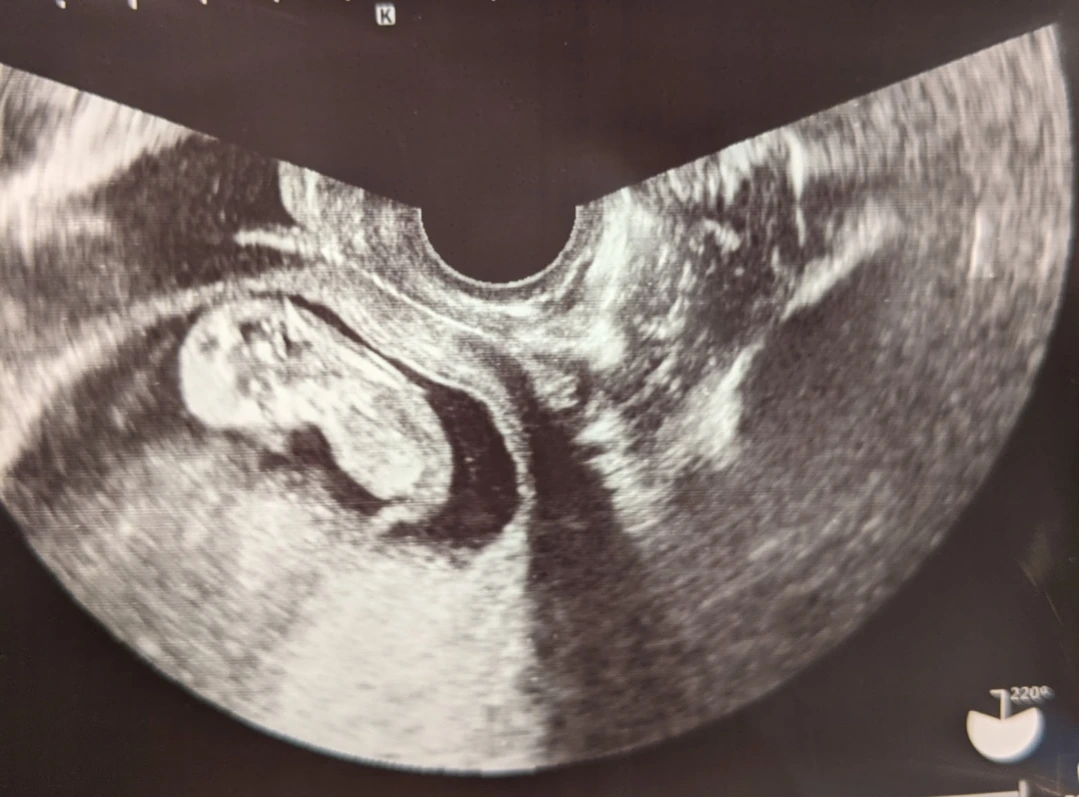

입덧으로 고생하는 와중에도 아기는 쑥쑥 잘 커주고 있었다. 임신 11주 차 초음파 사진. 머리와 몸통이 마치 땅콩 같다. 사진에서는 안 보이지만 팔다리도 이때 이미 생겼었다.

알아서 영양분 잘 흡수하고 있는 아기